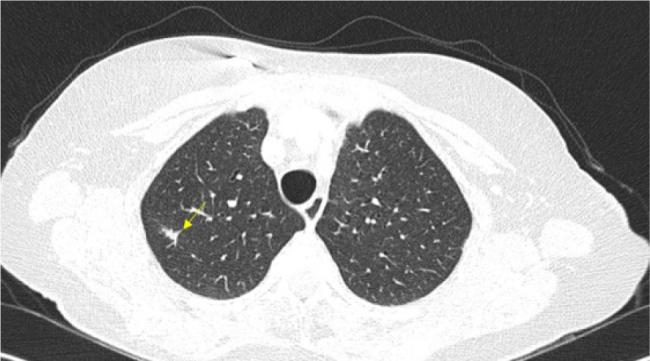

尿路上皮癌是全球最常被诊断出的癌症类型之一,尽管治疗取得了进展,但在转移阶段它仍然是一种致命疾病。由于其程序性细胞死亡配体1蛋白表达水平高,它与对免疫检查点抑制剂的反应增加有关。在过去几年中,转移性尿路上皮癌一线治疗的金标准一直是铂类化疗,以及对无进展肿瘤进行阿维鲁单抗(一种PD - 1抑制剂)维持治疗。在EV - 302研究显示出显著疗效后,指南最近进行了修订,将恩沃利单抗联合帕博利珠单抗纳入该情况下的新治疗标准。尽管有新的建议,但在一些国家,这种联合治疗仍有待批准。此外,对于不符合恩沃利单抗联合帕博利珠单抗治疗条件的患者,铂类化疗后进行阿维鲁单抗维持治疗仍然是首选的治疗方案。本报告介绍了一名被诊断为转移性尿路上皮癌的女性,在接受顺铂和吉西他滨化疗以及阿维鲁单抗维持治疗后,组织学证实完全缓解,这种情况在文献中仅有少数病例报道。